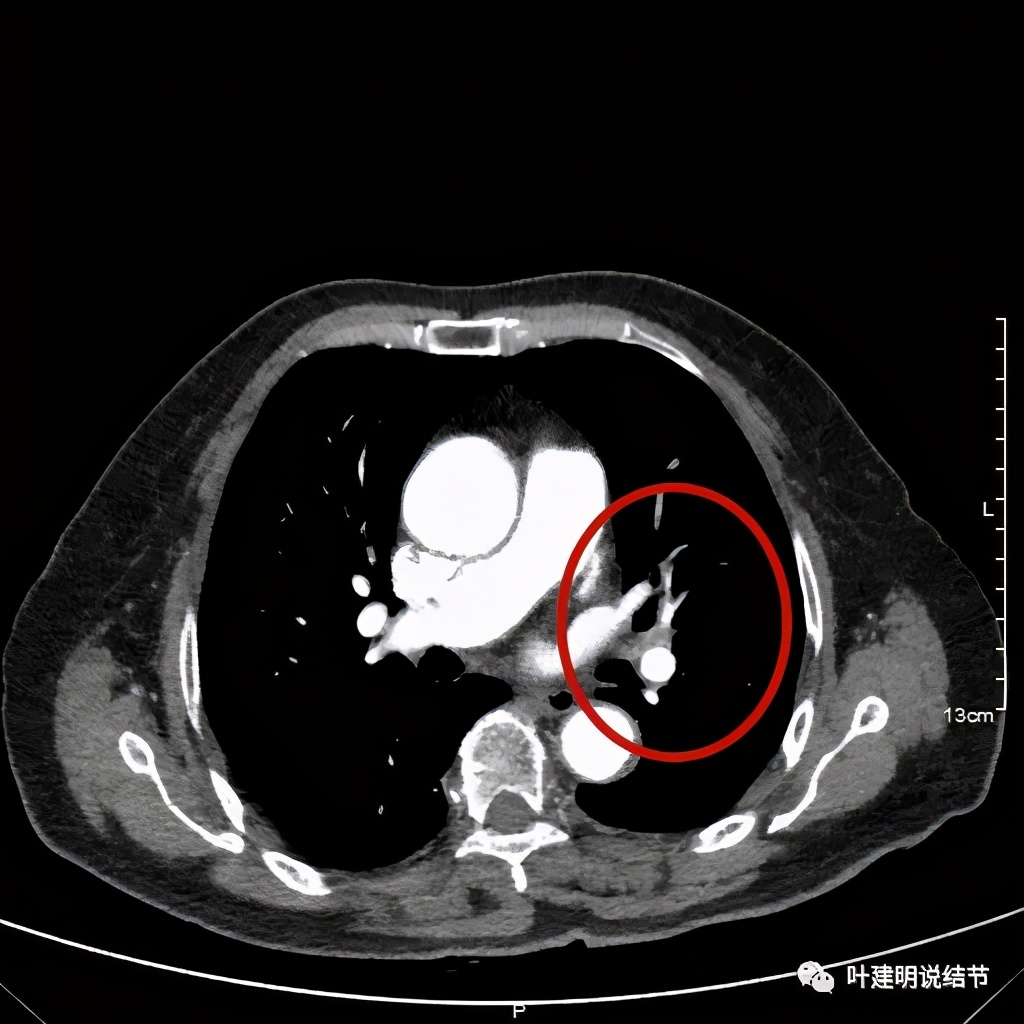

上图示肿瘤部位仍与肺动脉关系密切,似乎未能脱开,红色示肿瘤处

我样的治疗效果,显然超出了我们之前的预期,那么接下来拟选择行手术治疗,初定左上叶袖式肺叶切除加淋巴结清扫,但因为肺门区仍有软组织影,与肺动脉的关系仍密切,肿瘤与肺动脉间能否游离开来还是未知数,但至少得努力争取,鉴于患者年纪虽大,肺功能指标尚可,血气分析也基本正常,所以与患方沟通后确定行手术探查,但也也说明有万一全肺切除的可能(虽然这种可能性较小)。